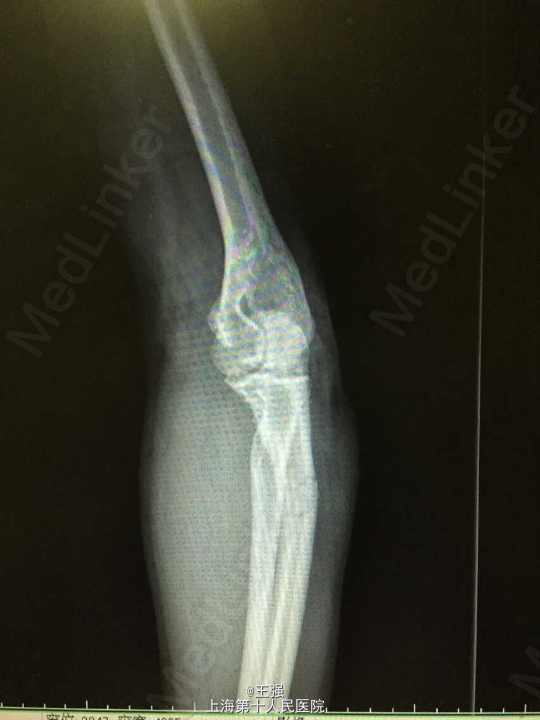

患者男,72岁 主述:左前臂外伤后肿痛、畸形、活动障碍1小时 病史:患者1小时前因外伤致左前臂肿胀、疼痛、畸形、活动受限,无头晕恶心,无出血,无手指麻木,无其他部位受伤,病程中患者无黑朦晕厥,无发热,无意思丧失,无胸闷胸痛,无恶心呕吐,无明显头晕头痛,于我院急诊拍片示:"左尺骨近端、远段骨折”,为进一步治疗,拟尺骨骨折收入院。 患者有高血压病史12年,最高150/90mmHg,自服药物(具体不详)血压控制可。

查体:神清,呼吸平稳发育正常,营养中等,查体合作。全身皮肤无淤点淤斑,无皮下出血,无肝掌蜘蛛痣。颜面部可见浮肿,全身浅表淋巴结未及肿大。颈软,气管居中,颈动脉搏动正常,颈静脉无怒张,心肺无特殊。无异常血管征。腹平坦,全腹软,未及包块,无压痛,无反跳痛,肝脾肋下未及,无移动性浊音,无肾区叩击痛,肠鸣音正常。四肢活动可,双下肢凹陷性水肿,足背动脉搏动正常,生理反射存在,病理反射未引出。 专科情况:左尺骨近端及远端肿胀明显,压痛(+),叩痛(+),可及骨擦音、骨摩擦感,远端手指运动、感觉及血运可,右上肢及双下肢正常。 辅查:X线片:左尺骨近段、远段骨折。

诊断:1.尺骨骨折(左,近端及远端) 2.高血压 治疗:入院后完善相关检查,控制血压,排除手术禁忌症后行骨折切开内固定术,术顺,术后予以抗炎、补液及对症治疗。